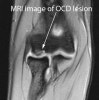

3. MRI : 관절면, 병변의 크기와 범위 평가

MRI : 박리성 골연골염(Osteochondritis dissecans)